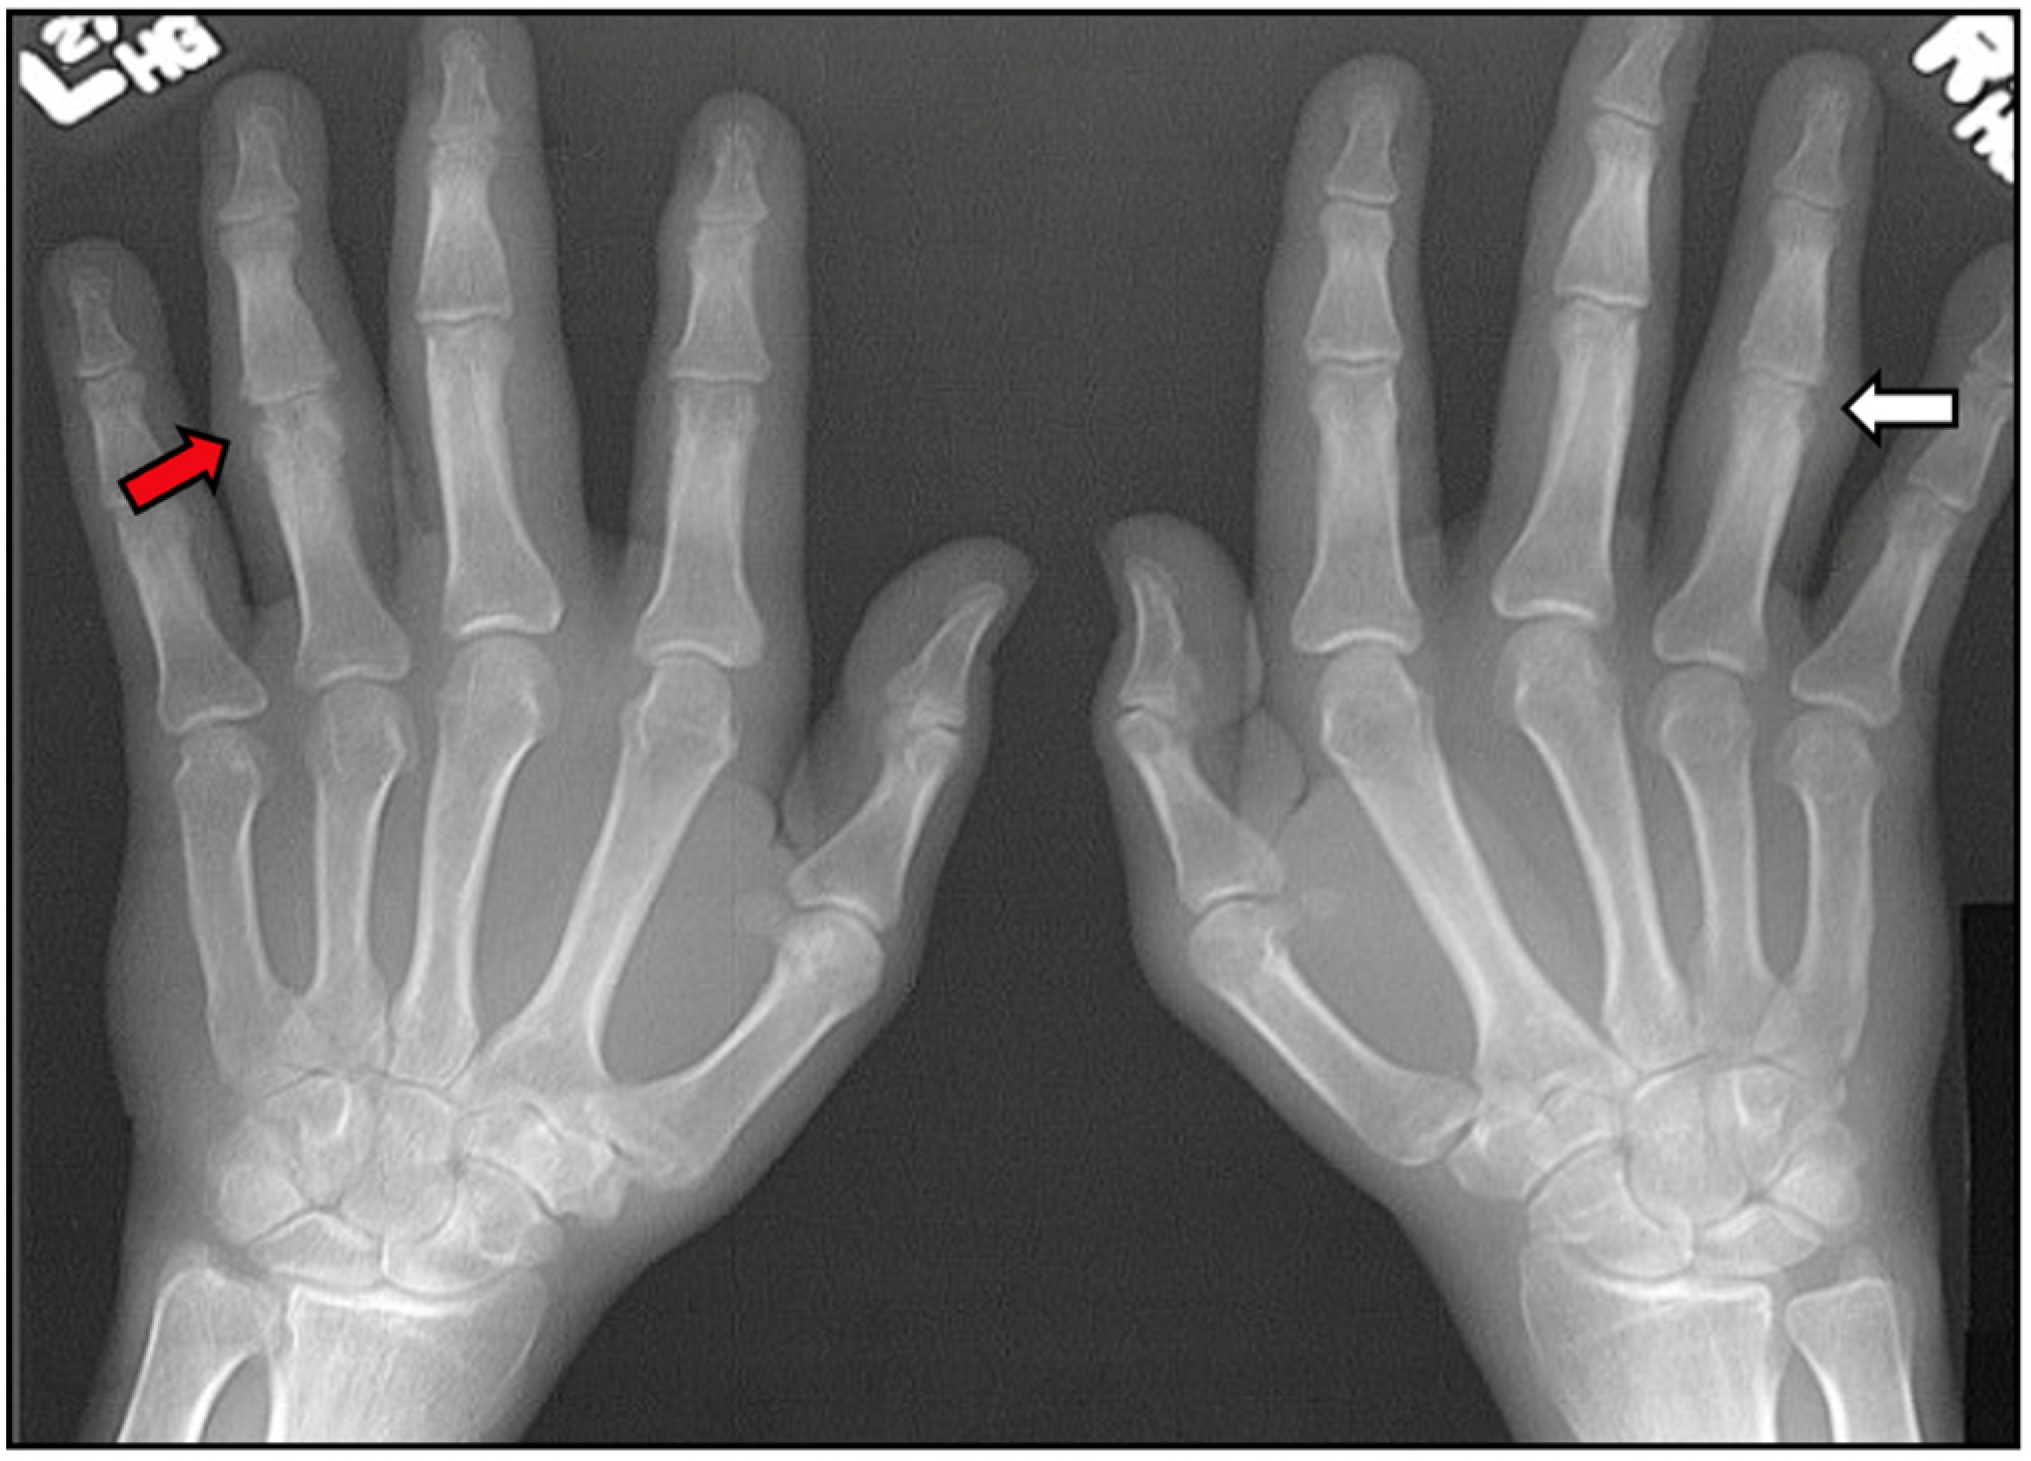

7.2.1. Plain Radiographs